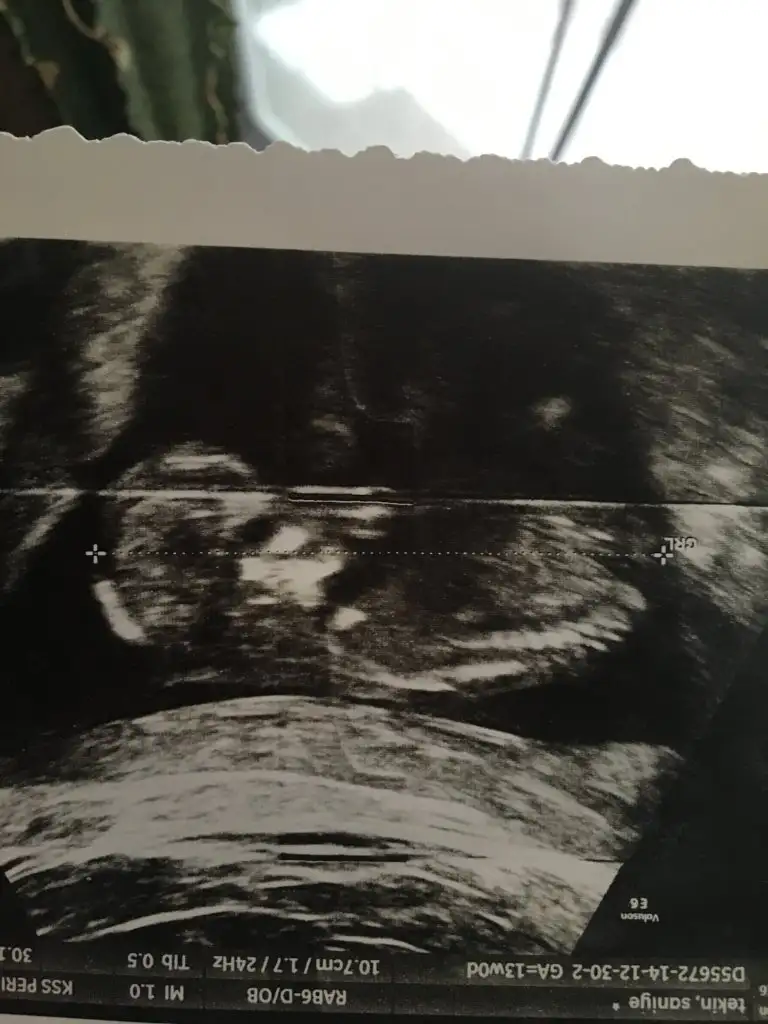

dr soylemeden siz gorun genital nub teorisi ( bebegin cinsiyeti)

Geçen hafta gitmiştim dr %80 kız demişti ama degişeblr dedi şmdi sizde böyle söylynce kadam karıştı 🧐